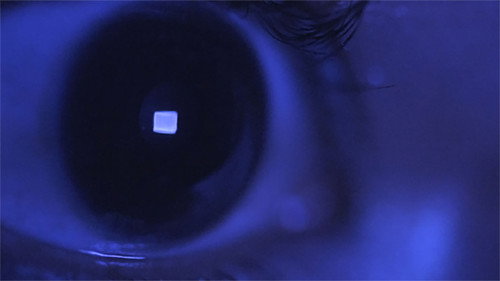

The adapter of an adapter